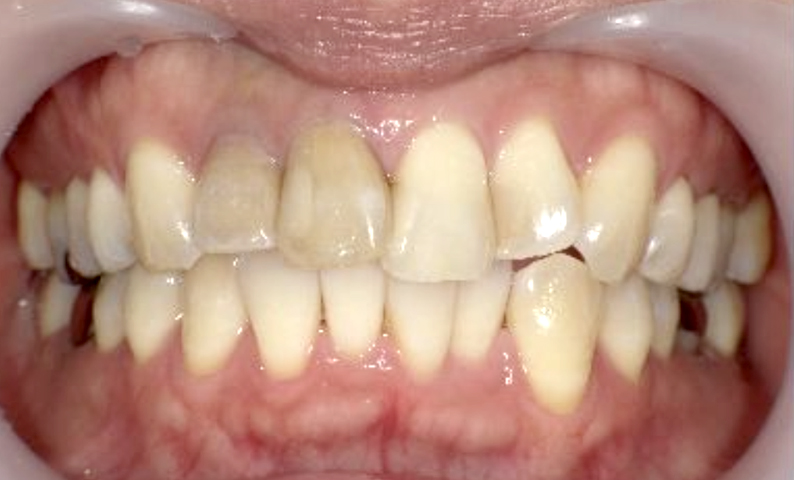

症例_003 上下顎の部分矯正

治療期間:12ヶ月金額:54万円+税男性八重歯前歯のガタガタ

| Before | After |